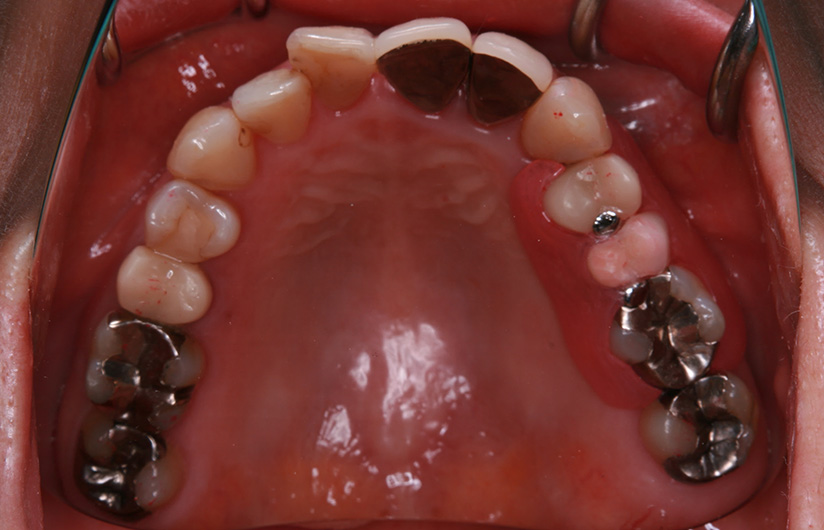

症例紹介

1歯義歯治療の例

術前・術後の比較

| 患者属性 | 50代 女性 |

|---|---|

| 主訴 | 左上の歯ぐきが痛む |

| 診断 | 左上5 歯根破折 |

| 補綴装置 | ノンクラスプデンチャー |

| 治療期間 | 約2ヵ月 |

| 通院回数 | 2回 |

| 治療費 | ノンクラスプデンチャー治療(1歯):110,000円(税込) |

| 治療内容 | 左上5の抜歯術を行い、治癒期間(約1か月)を得て、2回の義歯治療で義歯を作成しています。 |

| リスクと副作用 | 歯がないところの横の歯(隣在歯)に義歯をひっかけるため、その支えとなる歯には、ブリッジ治療と同様の影響があります。 |